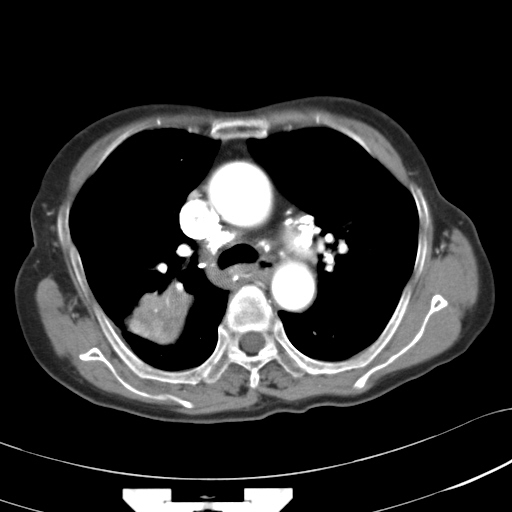

以下是引用hhcckk在2007-3-2 14:51:00的发言:[br]考虑结核球可能性大,依据[br]1病灶在下叶背段,结核的好发部位[br]2病灶内有大量的钙化,纵隔内有大量的淋巴结钙化[br]3重要的是半年前与现在相比无变化,假如是肿瘤的话不会这么‘善良’[br]4病灶周围卫星灶不明显,病灶有毛刺,胸膜凹陷,肿瘤不能完全排除,有条件的话最好做个活检